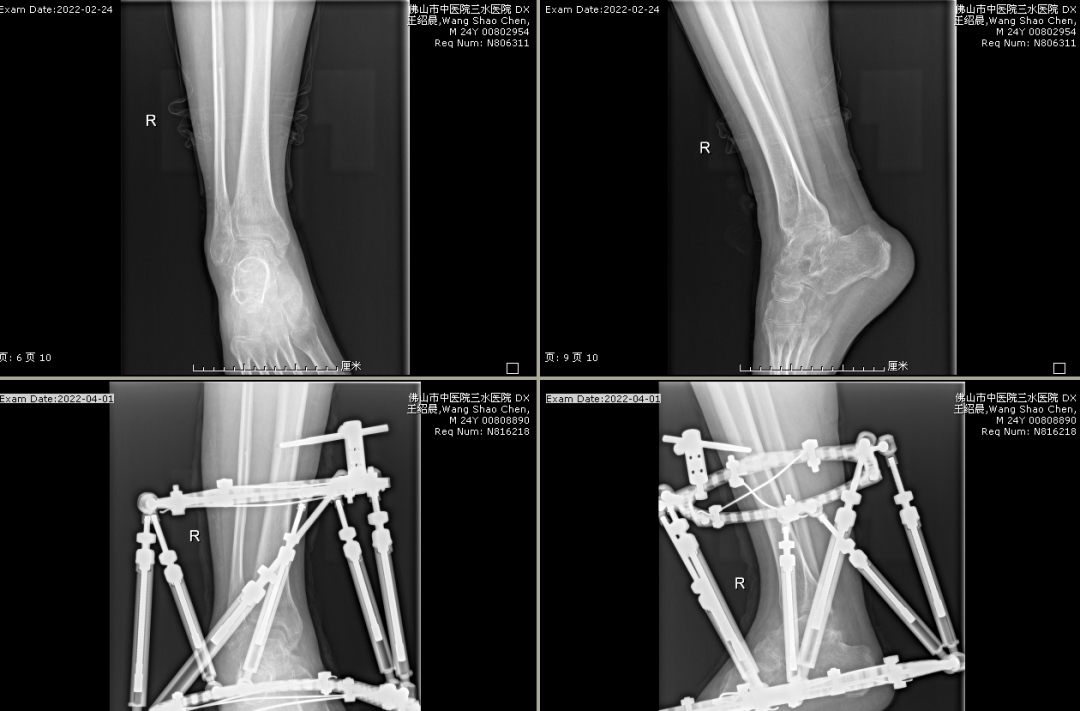

2019年,在广东省中医院的许树柴教授指导下,顺利完成我院首例膝关节单髁置换手术(UKA技术),2015年谢学文主任率先我科开展运用MIPO技术结合中医正骨手法微创治疗四肢干骺端骨折。继而,李伟强主任开展小儿陈旧性孟氏骨折矫形内固定术、截骨矫形支架外固定术、胫骨近端高位截骨矫形手术(HTO技术)、桡骨头置换术及骨搬运技术等。近年,在涂泽松主任指导下,更开展了肩关节置换术及进一步改善支架矫形技术。为我院创伤骨科矗立一座座里程碑。

目前,科室基本形成以四肢创伤骨折(闭合骨折、开放骨折、内固定取出等)、小儿骨骼创伤及创伤后遗留畸形(小儿肘部骨折及畸形,膝关节发育性畸形,踝部创伤后畸形)、四肢筋伤(软组织损伤及膝、踝关节侧副韧带损伤)、膝关节骨性关节炎中符合“保膝”治疗的患者、骨病(骨质疏松症、急慢性骨髓炎等)、脊柱疾病(胸腰椎单纯性压缩性骨折、腰椎间盘突出症、颈椎病)以及胸部创伤(肋骨骨折及稳定型胸部挫伤)七大重点为核心的发展方向。

对临床上不稳定型、复杂型四肢创伤骨折,运用“AO”、“BO”理念,施行闭合/切开复位钢板、髓内钉内固定术,对临床上开放性骨折施行清创复位内固定+支架外固定术;对临床上骨不连、骨缺损病例,施行切开植骨内固定/支架外固定术;对肘、腕、踝关节脱位合并骨折,运用有限切开复位克氏针内固定+胯关节外固定支架(可活动型),运用MIPO技术结合锁定钢板内固定治疗对四肢干骺端骨折进行微创治疗,运用单髁置换及HTO技术对膝前内侧骨性关节炎进行“保膝”治疗,运用桡骨小头假体置换治疗肘关节恐怖三联征;对开放性骨折脱位病例施行清创复位胯关节支架外固定术,有效降低肢体的感染率及伤残率。